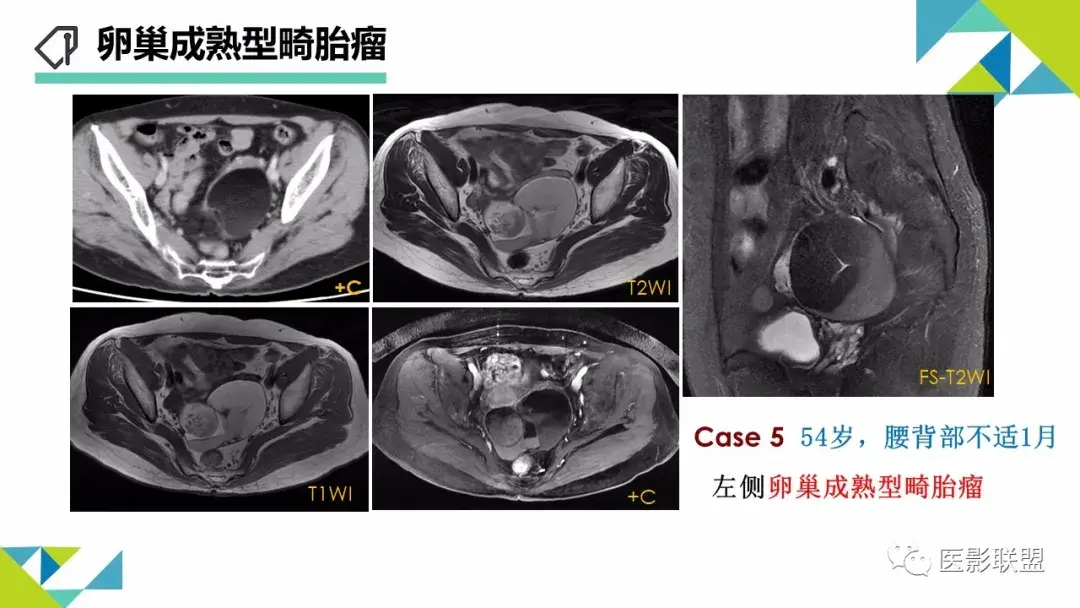

卵巢畸胎瘤的图像诊断及不典型征象分析

作者:刘红艳 清远市人员医院